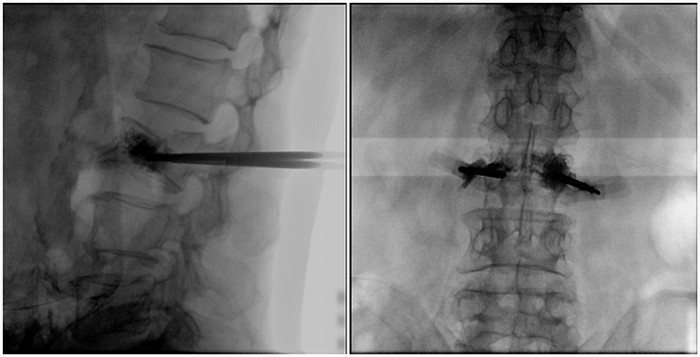

一體式移動(dòng)C臂腰椎影像

普愛醫(yī)療大平板一體式移動(dòng)C臂采用30cm×30cm的平板探測(cè)器,能在手術(shù)過程中,為醫(yī)生提供更廣闊的視野范圍,帶給醫(yī)生更全面的影像信息。在進(jìn)行脊柱類手術(shù)時(shí),一次曝光即可呈現(xiàn)全節(jié)段腰椎,避免因?yàn)槌氏癫蝗鴮?dǎo)致重復(fù)曝光,不僅提高了手術(shù)效率,而且避免醫(yī)生吸收過量的輻射。